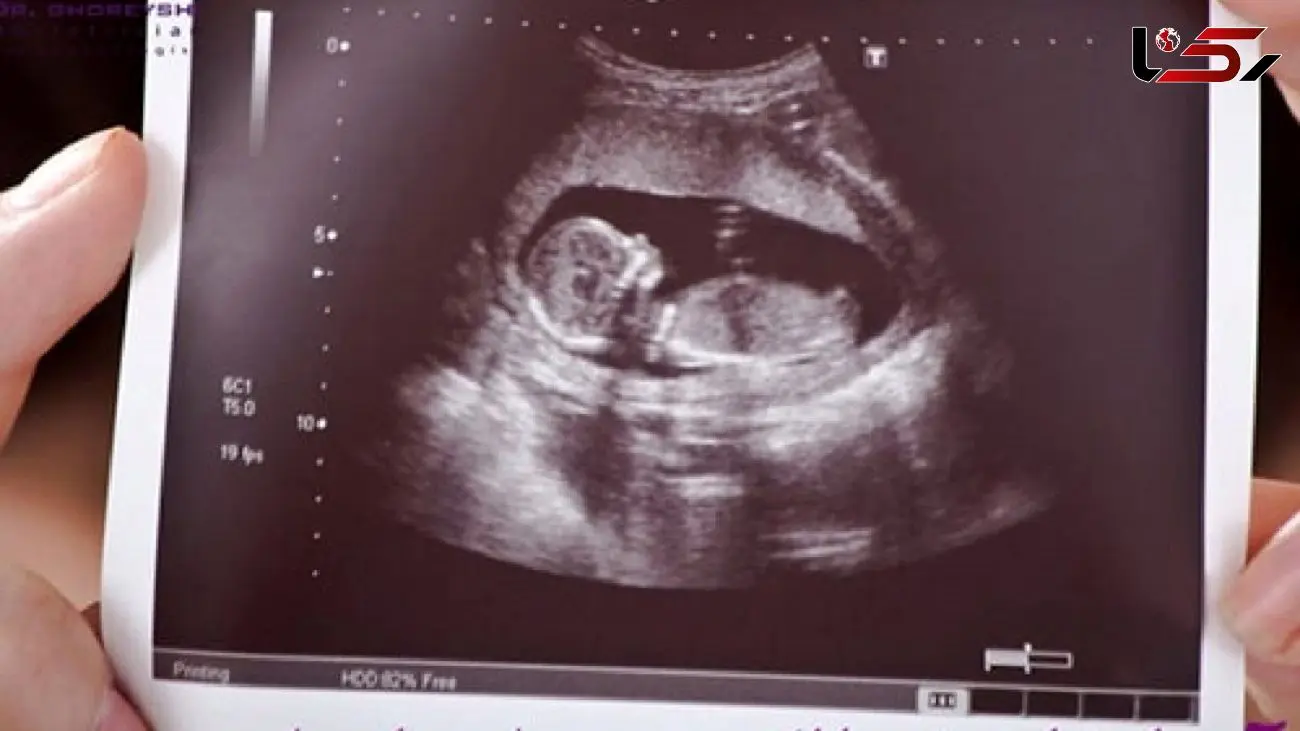

بیمه شدن هزینه سونوگرافی بارداری

رکنا: مسئول دبیرخانه قرارگاه سلامت و جوانی جمعیت وزارت بهداشت، درمان و آموزش پزشکی گفت: هزینه آزمایش‌های تصویربرداری های مربوط به مادر و جنین تحت پوشش بیمه پایه و تکمیلی قرار خواهد گرفت.

به گزارش رکنا، صابر جباری افزود: بر مبنای تبصره ۴ ماده ۵۳  هزینه آزمایش‌های تصویر برداری های مربوط به مادر و جنین از جمله انواع سونوگرافی بارداری تحت پوشش بیمه پایه و تکمیلی قرار خواهد داشت و از این جهت قانون گذار دغدغه هزینه های تشخیصی و درمانی برای همه مردم به ویژه برای خانواده های محروم و بی بضاعت را به خوبی دیده است.